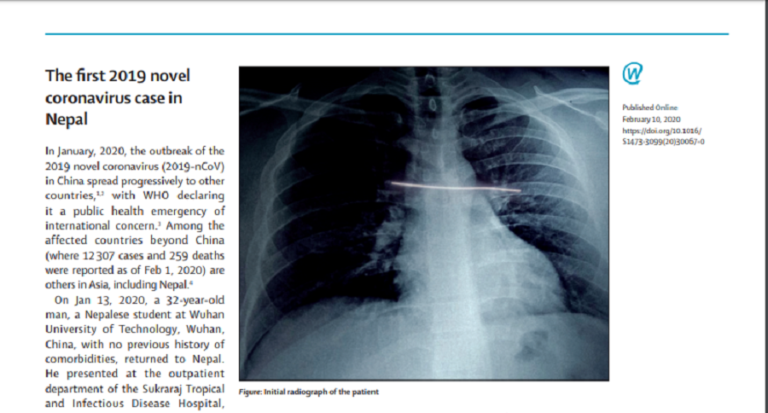

राष्ट्रिय जनस्वास्थ्य प्रयोगशालाकी निर्देशक डा. रुना झासहित स्वदेशी र विदेशी गरी १२ जनाले लेखेको जर्नल आर्टिकलमा युवकको उपचार र स्वास्थ्यमा के अवस्था आएको थियो सबै उल्लेख छ । युवक १३ जनवरी सन् २०२० मा कोरोना भाइरसका संक्रमित फेला परेका थिए । उनी वुआनस्थित वुआन युनिभर्सिी अफ टेक्नोलोजीमा रोगको कुनै पुरानो इतिहास नभएको अवस्थामा फर्किएको उल्लेख छ ।

युवक शुक्रराज ट्रपिकल तथा सरुवा रोग अस्पतालमा खोकी लागेको अवस्थामा पुगेको भनिएको छ । उनी ३ जनवरीमा विरामी भएको अवस्थामा आउँदा नेपाल आइपुगेको छ दिन भएको थियो ।

उनको पिसिआर टेष्ट हङकङस्थित प्रयोगशालामा पठाइँदा कोभिड १९ पत्ता लागेको थियो । युवक अस्पताल भर्ना हुँदा ९९ डिग्री फरेनआइटको तापक्रम थियो । घाँटीमा केही असजिलो अनुभव गर्दथे तर कुनै अन्य लक्षणहरु थिएन ।

ती युवकलाई आइशोलेशनमा राखेर उपचार गरिएको र छ घन्टापछि स्वास प्रश्वासको सामान्य समस्या आएको थियो । अस्पतालमा राखिंदा नियमित निगरानीमा राखिएको र १६ जनवरीमा डिस्चार्ज गरी घरमै सेल्फ क्वारेन्टाइनमा बस्न भनिएको जर्नल आर्टिकलमा उल्लेख छ ।

अन्य विरामीको तुलनामा भन्दा ती युवक १३ दिनमै नीको भई घर फर्किएको विषय उल्लेख गरिएका ेछ । नीको भएका अन्य विरामीको समेत तुलना गरी लेखमा उल्लेख गरिएको छ । त्यतिबेला युवकमा ज्वरो र खोकी मुख्य लक्षण देखिएको बताइएको छ ।